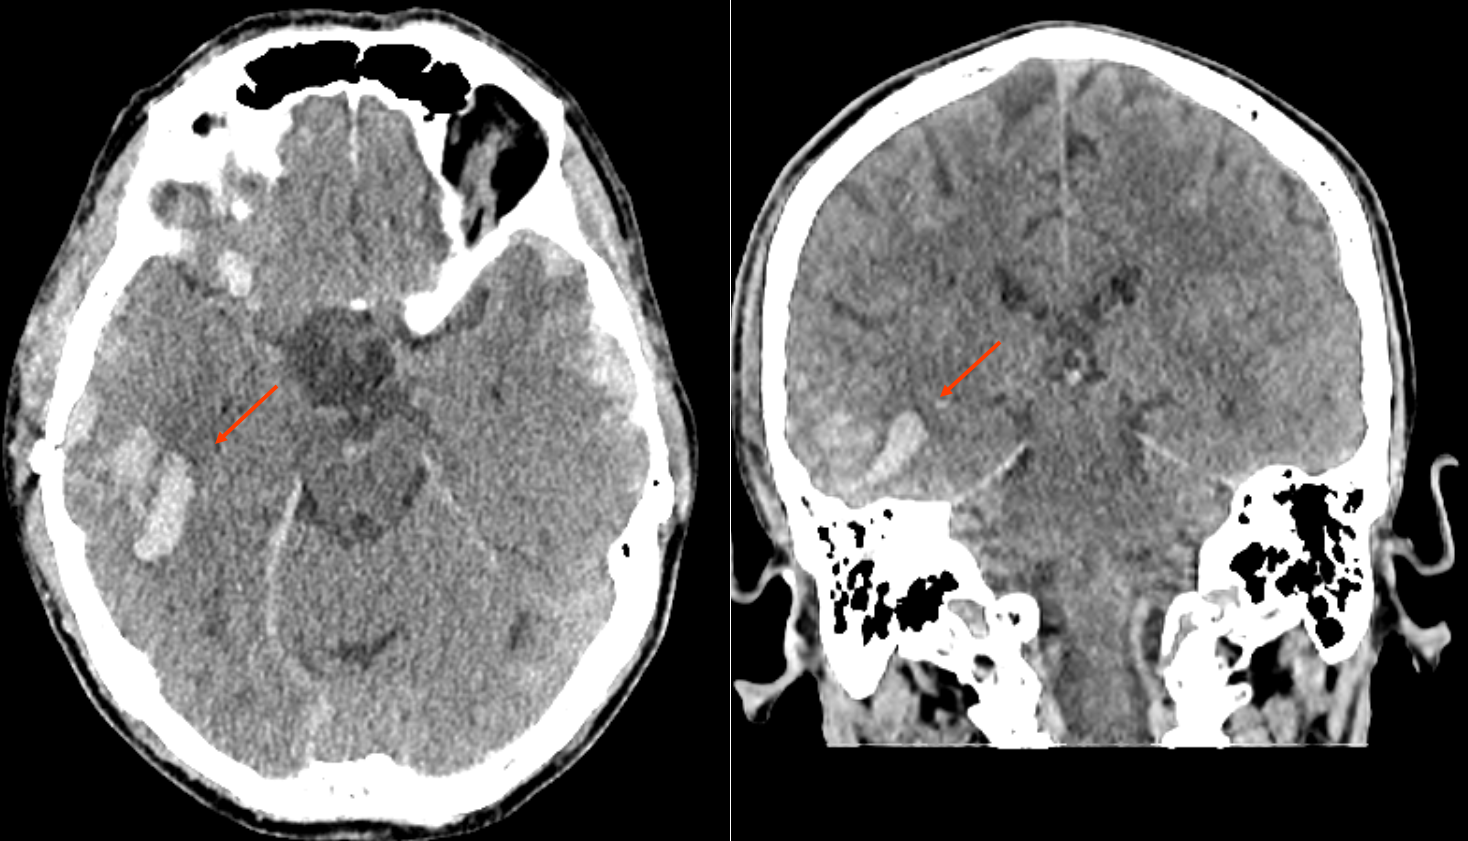

Kontusionsblutungen sind eine Form von intrakraniellen Blutungen, die häufig als Folge eines Schädel-Hirn-Traumas auftreten. Sie sind durch Blutungen innerhalb des Gehirnparenchyms gekennzeichnet, die oft in der initialen Bildgebung nicht oder nur geringfügig erkennbar sind, jedoch im Verlauf deutlich an Volumen zunehmen können. Diese Blutungen entstehen typischerweise durch eine rasche Dezeleration und den dadurch verursachten Aufprall des Gehirns gegen den Schädelknochen, basierend auf dem Coup- bzw. Contrecoup-Prinzip.

In der Bildgebung können Kontusionsblutungen mittels Magnetresonanztomographie (MRT) sowie Computertomographie (CT) dargestellt werden. Beide Methoden bieten unterschiedliche Vorteile: Während die MRT besonders bei der Darstellung des Weichteilgewebes und der Identifizierung älterer Blutungen effizient ist, bietet die CT Bildgebung den Vorteil einer schnelleren Verfügbarkeit und ist somit besonders in der initialen Notfallsituationen und Verlaufsbildgebung von Bedeutung.